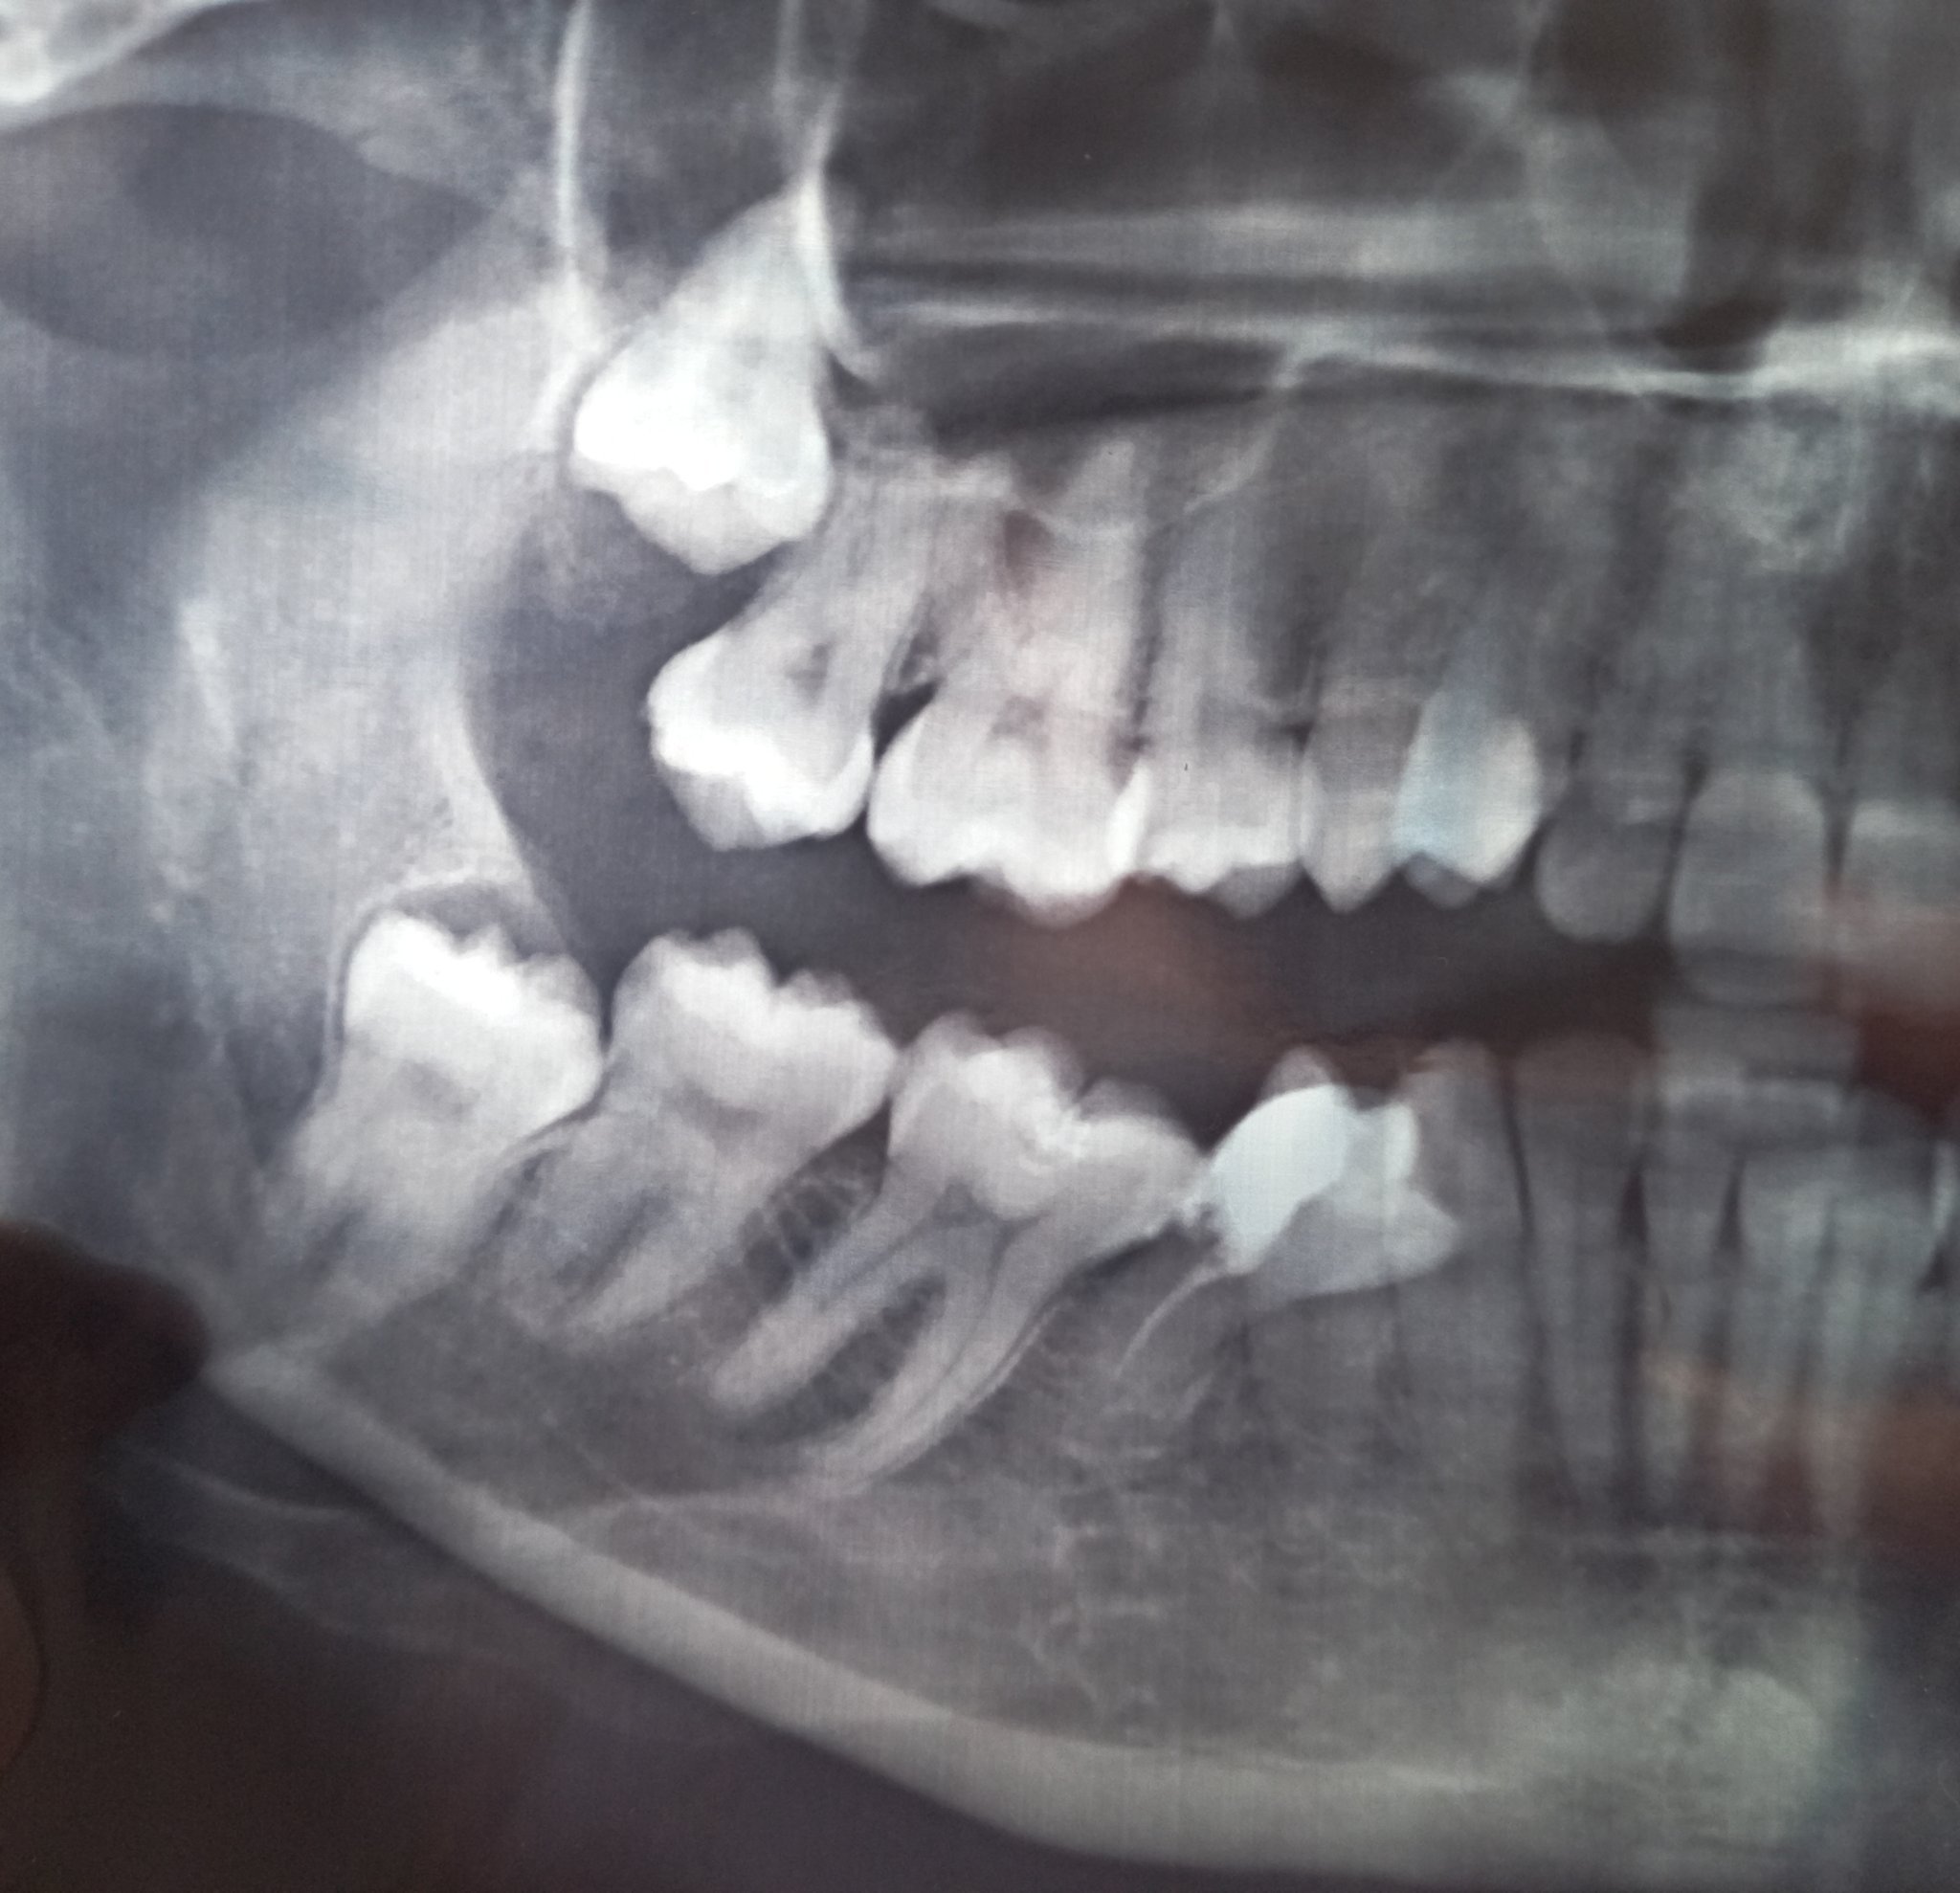

Здравейте, след недобро кореново лечение и поправки от неизчистен кариес(5ти ляв долен зъб,беше и леко крив ) получих пулсации около зъбите от 4ти наляво чак до венеца.Има миризма на гной, на снимка не излиза от къде е локализирана гнойта.Премахнаха ми зъба, но състоянието продължава.Пулсации без болка и миризма на гной от някъде.Някой експерт може ли да каже на какво се дължи и как да се открие проблема.Имам отпадналост и сърцебиене, безапетитие от тогава.Възможно ли е около костта да гнои или под съседни зъби да е преминало възпалението?